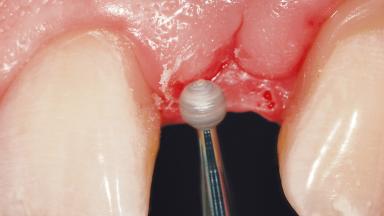

In the fall of 2003, a female patient was referred to the School of Dental Medicine, University of Geneva, for treatment of a traumatic fracture of a maxillary left lateral incisor. While at home, the patient fell down and hit a heating radiator with the anterior maxilla. During the initial examination, a week after the accident, the patient was in good general health condition and signs of pain/discomfort or clinical/radiographic infection were not observed. A moderate and localized hematoma with associated swelling persisted on the left side of the upper lip. Clinical assessment revealed a horizontal fracture at the cervical third of the anatomic crown of the maxillary left lateral incisor. In addition, a vertical crack line projecting into the cementoenamel junction (CEJ) called for a comprehensive assessment of the tooth restorability options.